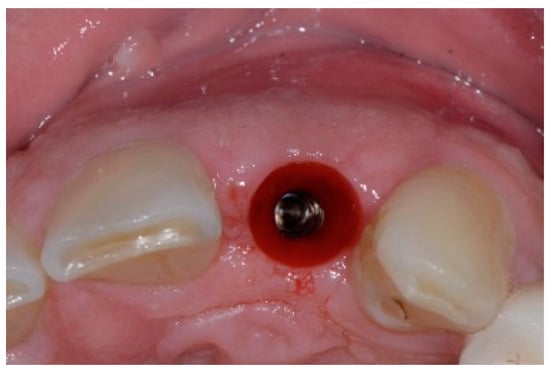

One hour before the surgical procedure, the patient received a prophylactic dose of 1 g of amoxicillin. Following local anesthesia, surgical access was obtained by raising a full-thickness aesthetic flap extending to the distal line angles of the lateral incisors. The full-thickness flap was extended 3–5 mm beyond the apical margin of the defect. The two central incisor roots were extracted, and the sockets were curetted with surgical curettes to remove all the granulation tissue (Figure 2). The sockets were assessed for the presence of a dehiscence and or fenestration. Two implants (Adin Dental Implants, Englewood, NJ, 07632, USA) were placed according to the manufacturer’s instructions (Figure 3).

Figure 3.

Clinical view of the placement of two maxillary anterior implants.